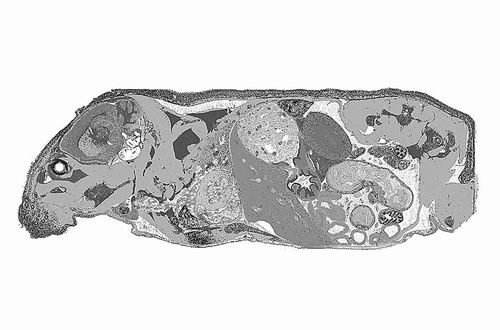

运用新技术生成的图像展示了经细菌毒素处理的整只小鼠横截面。图片来源:MARGARETTE CLEVENGER

Chevrier介绍,对于每张2厘米×6厘米的小鼠全身横截面切片,研究团队会利用约60万个检测点位来覆盖约500万个细胞。“一张切片就包含着海量信息。”

研究团队通过实验验证了该方法的应用潜力。他们给小鼠注射了可引发炎症的细菌毒素,从而检测全身基因表达的变化。结果发现,接受毒素处理的小鼠37个组织亚区和16类器官中的5000多个基因的活性有所增强或减弱。